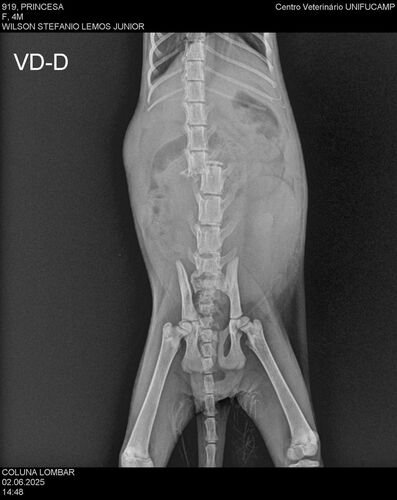

Durante as primeiras semanas com ela, investigamos as origens dela até conseguirmos o contato do homem que a encontrou. Conversamos com ele e soubemos que, ao resgatá-la, ele a levou para fazer exames e tentou viabilizar uma cirurgia na coluna. No entanto, o hospital recusou realizar o procedimento e sugeriu a eutanásia. Ele não queria aceitar essa opção, então, chegaram a um acordo: colocariam a gatinha para adoção e, caso ninguém a adotasse, fariam a eutanásia. Foi assim que ela entrou em nossas vidas.

Preocupadas com sua condição e buscando segundas opiniões, levamos a gatinha a uma veterinária especializada em fisioterapia. Após analisar os exames, ela nos orientou a realizar a cirurgia, que pode melhorar muito sua qualidade de vida e até possibilitar que volte a andar. Por indicação dessa profissional, encontramos um veterinário que realiza o procedimento por R$ 2.500,00.